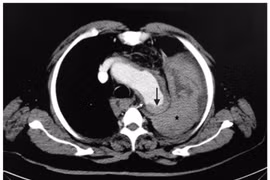

(khoahocdoisong.vn) - Lóc tách động mạch chủ (LTĐMC) trước hay gặp ở độ tuổi từ 60 – 70 nhưng hiện tại nhiều thanh niên khỏe mạnh tự nhiên đau ngực và ngất xỉu vì bệnh. Đây là một một thảm họa thực sự của bệnh tim mạch.